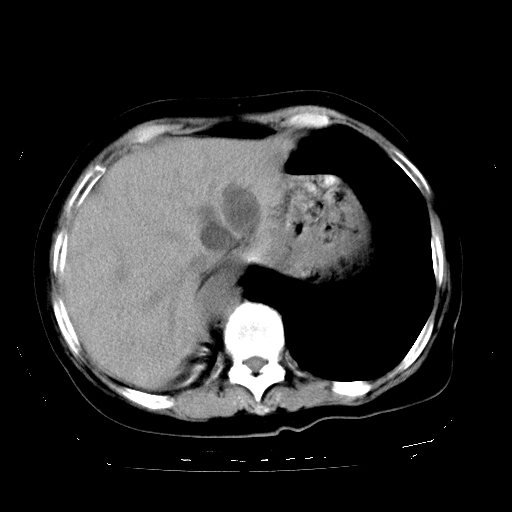

标题: CT23991:女,72岁,咳嗽、憋气一周。 [打印本页]

女,72岁,咳嗽、憋气一周,十年前曾患肺结核及胸膜结核。

1.右侧损毁肺伴胸膜钙化,2.左肺小结节灶,良性可能大,注意复查。3.肝脏左叶囊肿。4.先天性一侧肺不发育待出外(右侧胸廓无明显塌陷)。对比原片应该非常有帮助。

支持楼上,肝脏多发囊肿